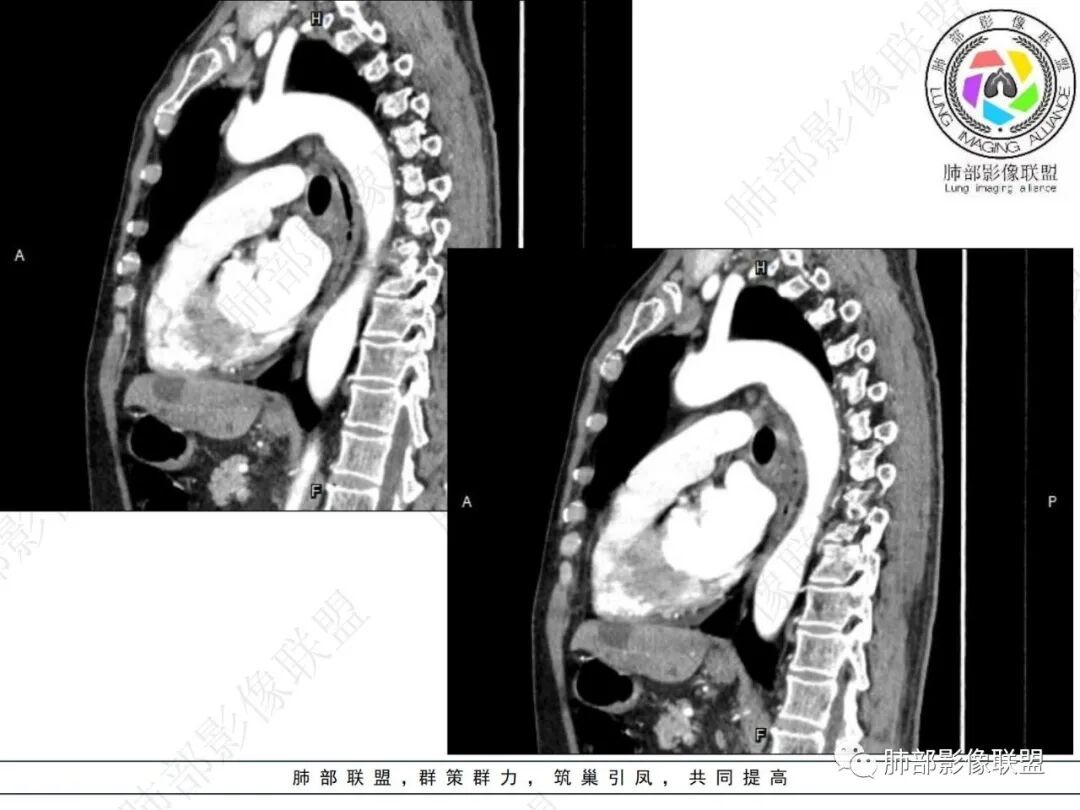

右肺下叶背段可见斑片状、条片状高密度影,支气管扩张,周围伴有磨玻璃影,边界欠清,纵隔窗:可见脊柱偏右侧可见斑片状影,与食管交界面欠清,食管形态不规则,考虑食管支气管瘘?食管异物穿孔?支气管异物?建议食管镜及支气管镜检查。

气管隆突下团片影,其内积气,与食道分界不清,食道壁增厚,管腔狭窄,右下肺实变影,支气管壁增厚,考虑食管支气管瘘并右下肺感染,食道肿瘤病变不除外

支持食管支气管瘘(考虑食管癌)伴后纵隔及右肺感染,食管管壁明显增厚,管腔狭窄,相邻右侧后纵隔内软组织内可见气体影,与食管分界不清,右肺有实变及不张。

右肺下叶背段条片状实变影,内可见支气管走行,支气管有狭窄有扩张,周围可见磨玻璃影,隆突下团片影,内密度不均可见气体影,与周围结构界限不清。食管下段壁增厚,管腔狭窄,右肺下叶慢性炎、肺不张,考虑食道肿瘤所致气管食管瘘。

右肺下叶沿肺叶肺段分布斑片、条片状影,以下叶背段为显,边缘模糊,内可见支气管走行,局部支气管管壁增厚,右侧胸腔少量积液。纵隔隆突下可见不均匀软组织密度影,与周围结构分界不清,内见气体密度影,与食管及相邻右肺支气管之间未显示通道。邻近食管下段壁明显不规则增厚,增强后食管管壁明显不均匀强化,可见线样强化的连续完整粘膜影。

对比患者3月份的CT图,原隆突下存在增大钙化淋巴结,现在出现气体影,且钙化显示不清,应想到淋巴结结核破溃成瘘可能性。